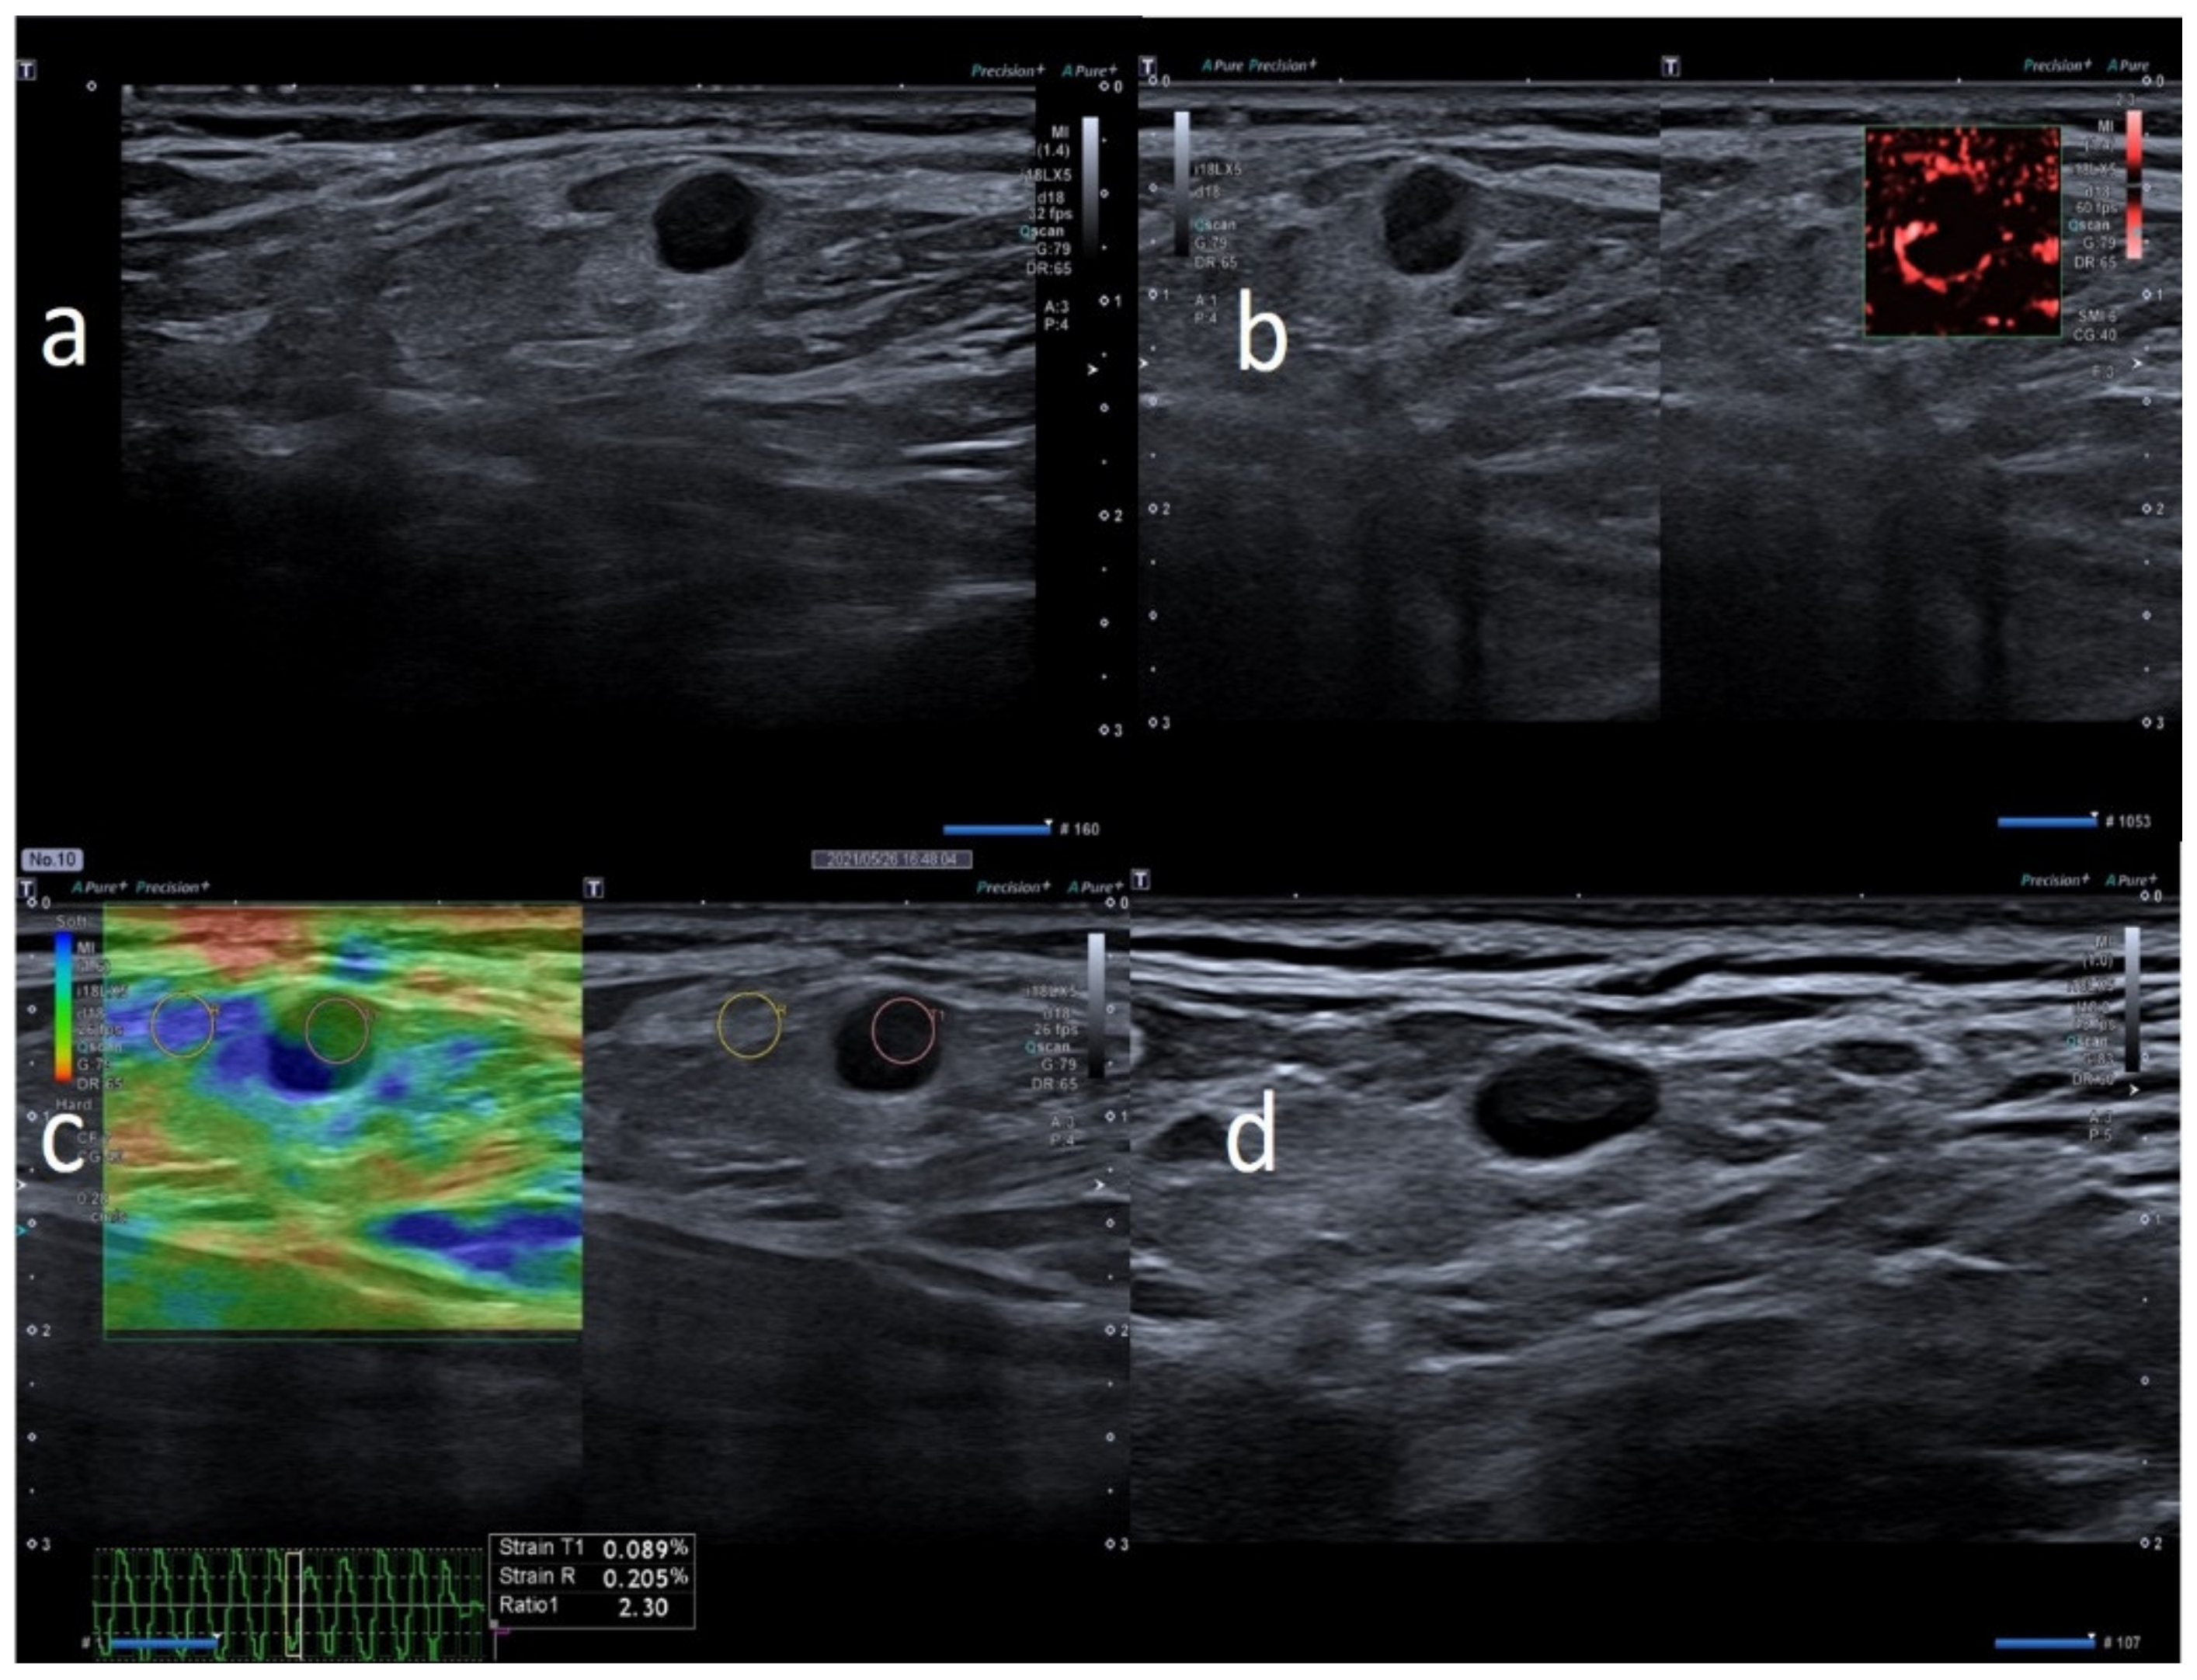

| M | 64 | Pfizer | Supraclavicular ipsilateral to vaccine injection | Occasional autopalpation 2 weeks after second dose vaccine | None | 2 | Around 1.0 cm | Ovular | Assimetric cortical thickening with hilum evidence | Stiffness similar to surrounding tissue | Normal | Unnecessary other follow-up |

| M | 42 | Pfizer | Axillary ipsilateral to vaccine injection | Occasionally 1 weeks after second dose during chest ct | None | 3 | Variable: from 1.5 to 2.0 cm | Ovular | Simmetric cortical thickening with normal hilum | Stiffness similar to surrounding tissue | Normal | Unnecessary other follow-up |

| M | 60 | Pfizer | Supraclavicular ipsilateral to vaccine injection | Occasional autopalpation 12 days after second dose vaccine | None | 2 | Around 1.0 cm | Ovular | Simmetric cortical thickening with normal hilum | Stiffness similar to surrounding tissue | Central and peripheral vascular signals | Unnecessary other follow-up |

| W | 54 | Pfizer | Axillary ipsilateral to vaccine injection | Occasionally, 14 days after second dose, during breast sonography for surveillance | None | 3 | Variable: from 1.0 to 2.0 cm | Ovular | Simmetric cortical thickening with normal hilum | Stiffness similar to surrounding tissue | Normal | Unnecessary other follow-up |

| W | 52 | Pfizer | Axillary ipsilateral to vaccine injection | Occasionally during breast sonography for oncological surveillance | None | 3 | Variable: from 1.0 to 2.5 cm. | Ovular | Simmetric cortical thickening with normal hilum | Stiffness similar to surrounding tissue | Normal | Unnecessary other follow-up |

| M | 62 | Pfizer | Axillary ipsilateral to vaccine injection | Occasionally, 2 weeks after first dose, during chest ct to monitor small polmonary nodules | None | 3 | Variable: from 1.5 to 2.0 cm. | Ovular | Simmetric cortical thickening with normal hilum | Stiffness similar to surrounding tissue | Normal | Unnecessary other follow-up |

| M | 57 | Pfizer | Axillary ipsilateral to vaccine injection | Occasional autopalpation 2 weeks after second dose vaccine | Kidney cancer 4 years ago | 2 | Around 1.0 cm | Ovular | Asimmetric cortical thickening with hilum evidence | Stiffness similar to surrounding tissue | Normal | Normalized to 30 days |

| M | 63 | Moderna | Axillary ipsilateral to vaccine injection | Occasionally, 16 days after first dose, during mammography | None | 3 | Variable: from 1.5 to 2.0 cm. | Ovular | Simmetric cortical thickening with normal hilum | Stiffness similar to surrounding tissue | Normal | Unnecessary other follow-up |

| F | 66 | Moderna | Supraclavicular ipsilateral to vaccine injection | Occasionally, 2 weeks after second dose, during shoulder rm | None | 2 | Around 1.0 cm | Ovular | Assimetric cortical thickening with hilum evidence | Stiffness similar to surrounding tissue | Central and peripheral vascular signals | Normalized to 30 days |

| M | 59 | Astrazeneca | Supraclavicular ipsilateral to vaccine injection | Occasionally, autopalpation 4 days after second dose vaccine | None | 2 | 0.7 and 1.2 cm | Ovular | Asimetric cortical thickening with hilum evidence | Stiffness similar to surrounding tissue | Normal | Unnecessary other follow-up |